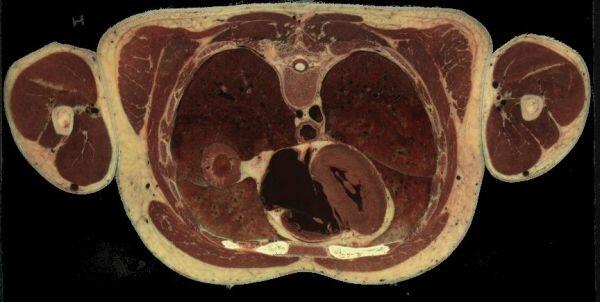

à 457 mm du sommet du crane, le coeur et son puissant myocarde au sein des deux blocs pulmonaires spongieux :